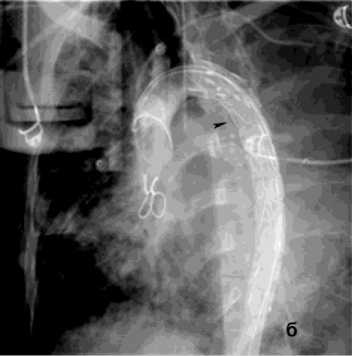

Рисунок 6. Ангиограмма БА у пациента с опухолью заднего средостения и прорастанием лёгкого, ЛК2Б: а – извитость и усиление лёгочного рисунка; б – состояние после эмболизации – окклюзия БА

Figure 6. Angiogram of the BA in a patient with posterior mediastinal tumor and lung invasion, PH grade 2B: a – tortuosity and increased pulmonary vascularity; б – status post embolization – occlusion of the BA